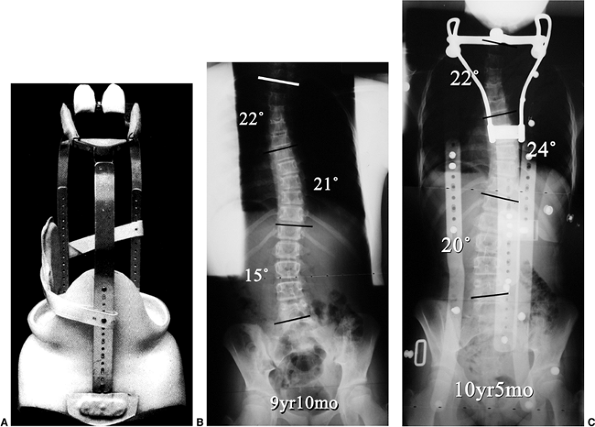

Figure 18.22 A: Milwaukee brace. B:

posteroanterior radiograph of a 9-year 10-month-old girl with juvenile-onset scoliosis that progressed and was treated with a Milwaukee brace. C: The subsequent in-brace radiograph demonstrates the superstructure. This brace was chosen primarily to help address the upper thoracic deformity.  |